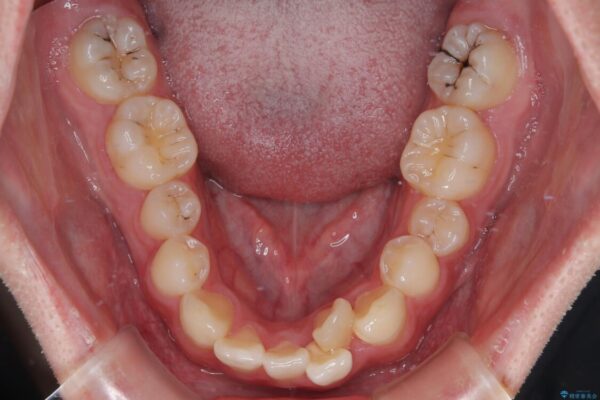

初診時の状態

・上下ともに歯がきれいに並びきらず、がたつきが見られました。

・上下の前歯の中心(正中)がずれています。

・特に上顎の幅が狭いため、下顎の歯列も内側に入り込み、歯が並ぶスペースが不足していました。

治療前

• 1年でここまで変わる!歯列のがたつきと正中のズレを改善した矯正治療(メタルブラケット×MARPE) 治療前画像